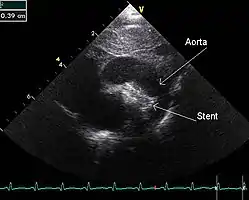

An echocardiogram of a stented persisting ductus arteriosus: One can see the aortic arch and the stent leaving. The pulmonary artery is not seen.